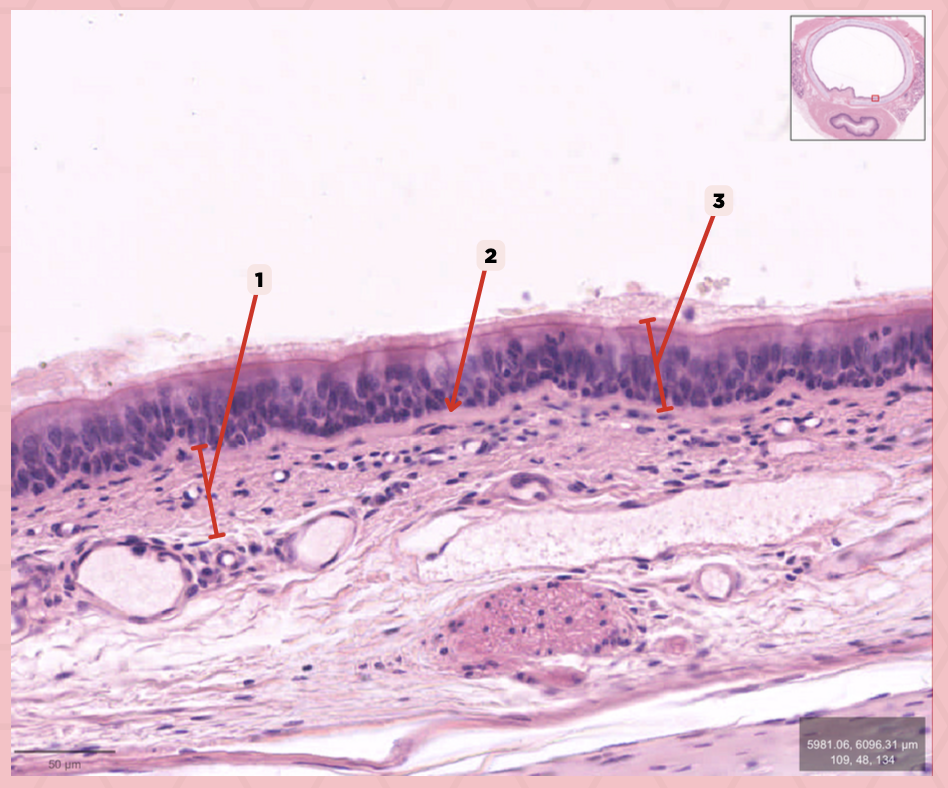

Respiratory Epithelium

Identify the structure labeled as 1.

Lamina Propria

Identify the structure labeled as 2.

Bony spicule

Identify the structure labeled as 3.